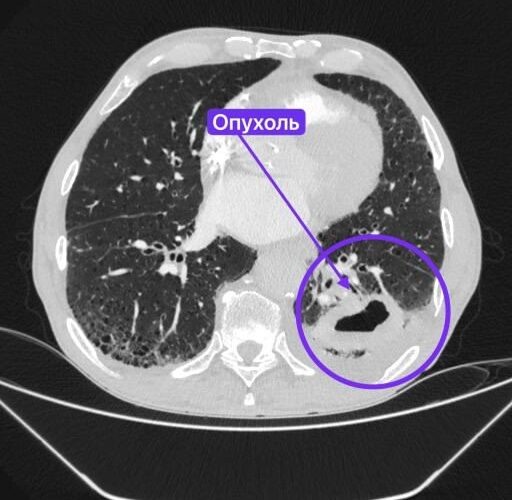

Медик направил мужчину в стационар, где он пролежал три недели. Врачи Нижнекамской ЦРМБ обследовали пациента и обнаружили образование, после чего рекомендовали взять направление к онкологу по месту жительства. Все это случилось под новогодние праздники. Поэтому к онкологу Вячеслав попал только в январе. Оказалось, что за это время в легком развился абсцесс, а на аорте образовалась аневризма.

Консилиумы в Набережных Челнах и Нижнекамске приняли решение, что мужчину невозможно оперировать в их условиях. В результате пациента направили в Казань. В РКБ его еще раз обследовали, взяли биопсию, чтобы определить характер опухоли.

«Оперировать легкое было опасно, аневризма, как бомба, могла разорваться в любой момент. Поэтому сначала за пациента взялись рентген-хирурги – установили стент-графт (устройство для укрепления стенок аорты), чтобы предотвратить разрыв аневризмы. Стент-графт подбирается индивидуально под каждого пациента. После чего мужчину наблюдали и лечили в отделении сосудистой хирургии. К моменту перевода в торакальное отделение №1 хирурги получили результаты биопсии», — поделились специалисты.

Выяснилось, что у Вячеслава была злокачественная опухоль, которая начала разрушаться. В итоге через мини-разрез убрали образование, пораженные ткани и лимфоузлы. Операция прошла успешно. Пациент достаточно быстро пошел на поправку. Сейчас мужчина уже дома. Ему предстоит пройти курс химиотерапии.